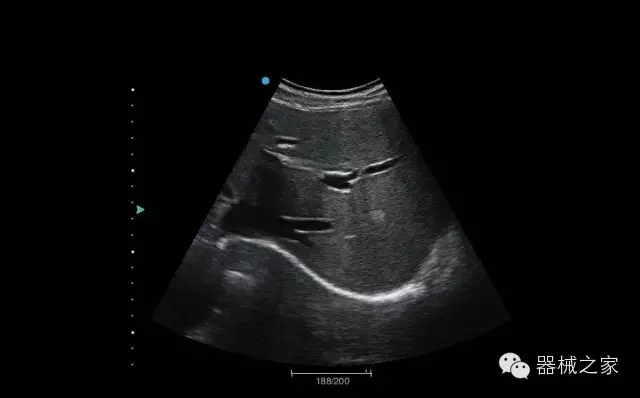

臨床圖片賞析

睪丸低速血流